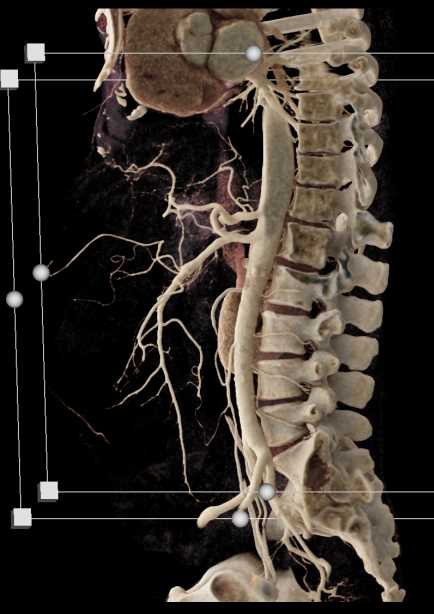

SMA Stenosis